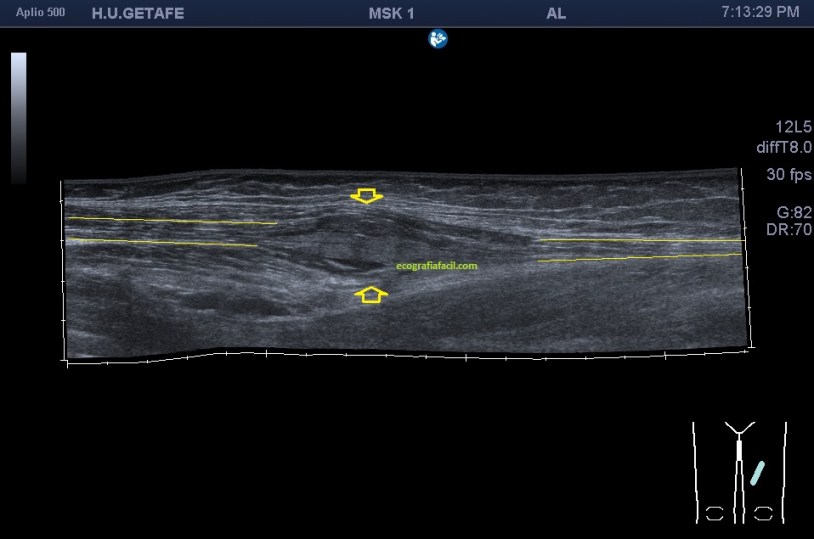

Imagen usando «PANORAMIC VIEW», donde observamos en un contexto amplio la lesión y la musculatura normal marcada por las líneas alargadas amarillas tanto proximales como distales.